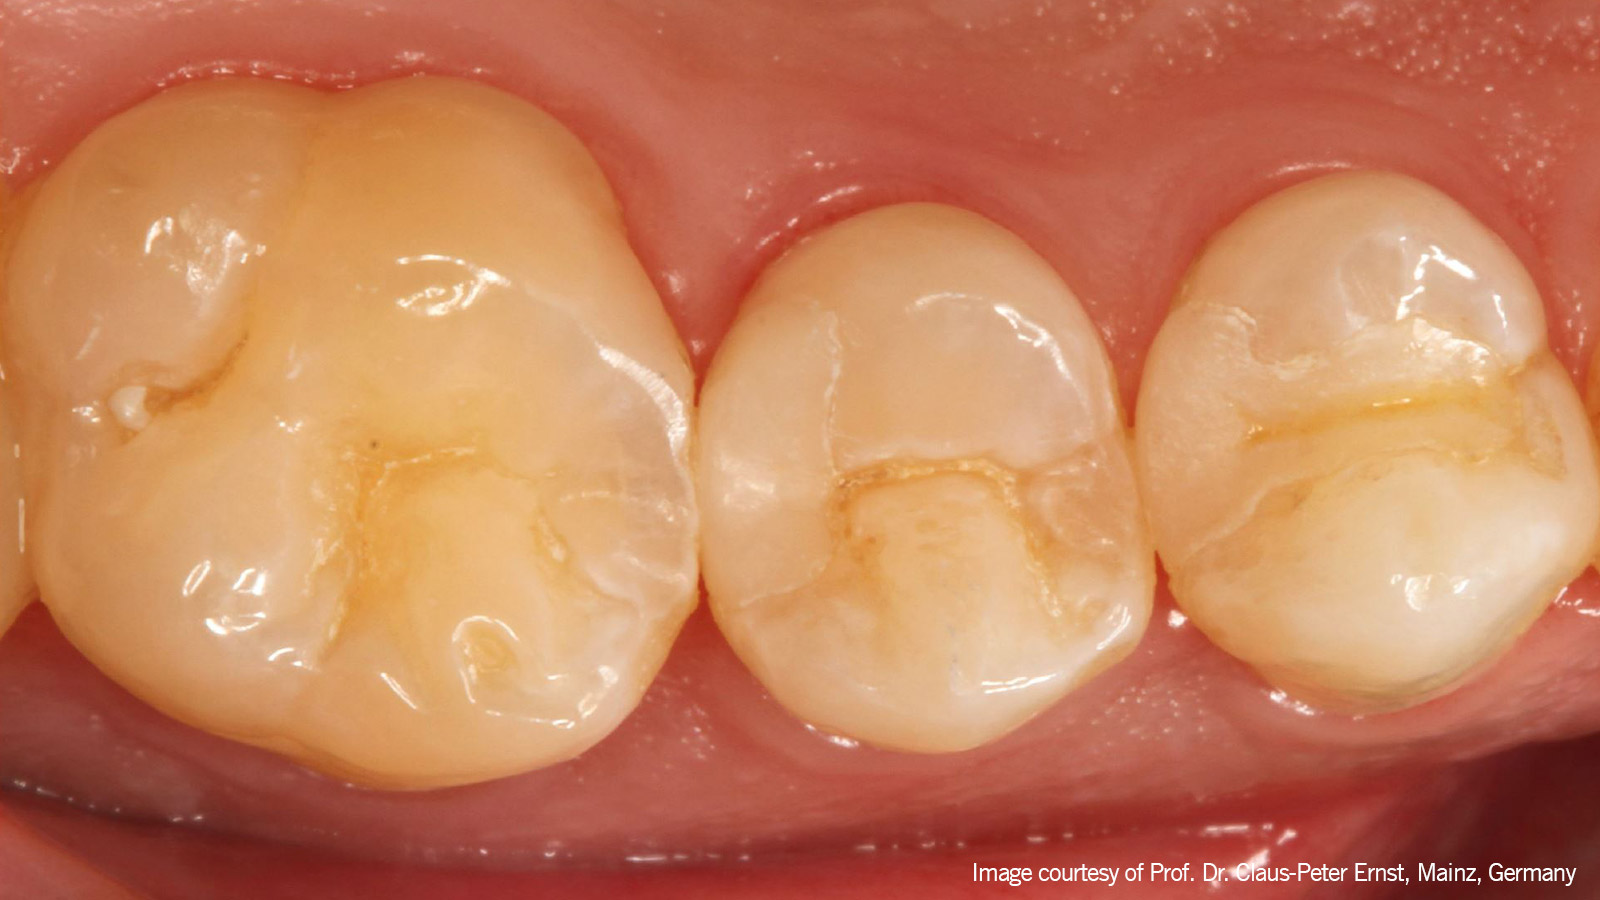

Dr. Ernst

Inlay als probleemoplosser voor occlusieproblemen?

diagnosis

Zeer kleine, recent geplaatste keramische inlays op elementen 14 en 15. Element 15 vertoonde aanhoudende pijn als de patiënt beet en een sterk verhoogde gevoeligheid voor kou. De vermoedelijke diagnose was een afwijking van element 15.